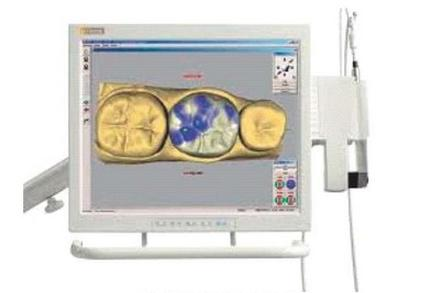

Aparat przedstawiony na zdjęciu służy do

A. leczenia kanałowego.

B. jonoforezy igłowej.

C. diagnostyki jamy ustnej.

D. badania żywotności miazgi.